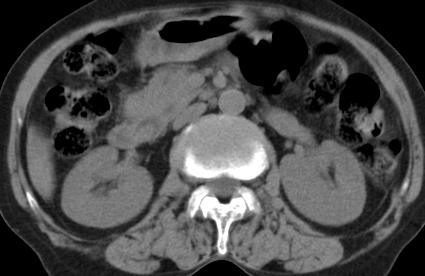

以下是引用齐原在2006-11-8 23:21:00的发言:[br]肝脏体积增大.肝表凸凹不平,肝内胆管扩张,胆总管扩张,胆总管末端突然截断,胰腺勾突增大,形态不规则.胰管扩张.考虑胰头癌.并低位梗阻性胆系扩张,胆囊炎.脾大.建议增强

以下是引用dyqct在2006-11-9 9:14:00的发言:[br]肝大,表面呈波浪状,肝内外胆管扩张,胆总管下端腔内见小结节状等密度影,胰管轻度扩张。胆囊显示不清。[br]考虑:1、胆总管下端占位性病变(等密度结石?壶腹部肿瘤?);[br] 2、肝硬化?[br] 3、建议增强扫描进一步检查。